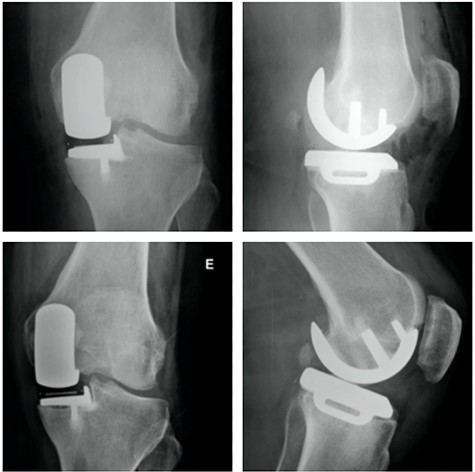

Orthostatic anterior view (A) and Rosenberg (B) X-ray images with medial osteoarthritis—right knee; Lateral view X-ray image of the same knee (C); T2 coronal MRI (D) with severe MP and femoral condyle SIFK; Immediate postoperative X-ray image (E) and 3 months after surgery (F) showing tibial component loosening.